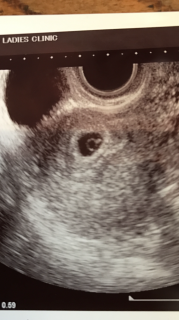

真ん中の白い輪っかは良い兆候で、もうすぐ赤ちゃんも見えるそうです。一ヶ月後には今通っているレディースクリニックから産院に転院なのでどこで出産するか選び始めるよう言われました。次の検診は2週間後、順調に育ってくれるといいな。

2人目妊娠です☆袋確認できました!とりあえず、ちゃんと子宮にいた~今、1センチだそうです。つぎは2週間後、心拍確認できるといいなぁ!このまま順調に大きくなぁ~れ!!